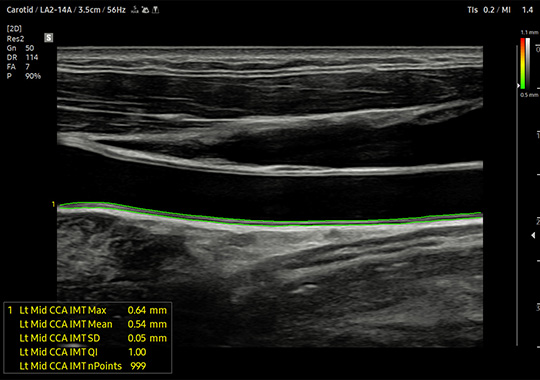

LA2-14A

- Wide Band Linear

- Application: Abdomen, Musculoskeletal, Pediatric, Small Parts, Thoracic, Vascular